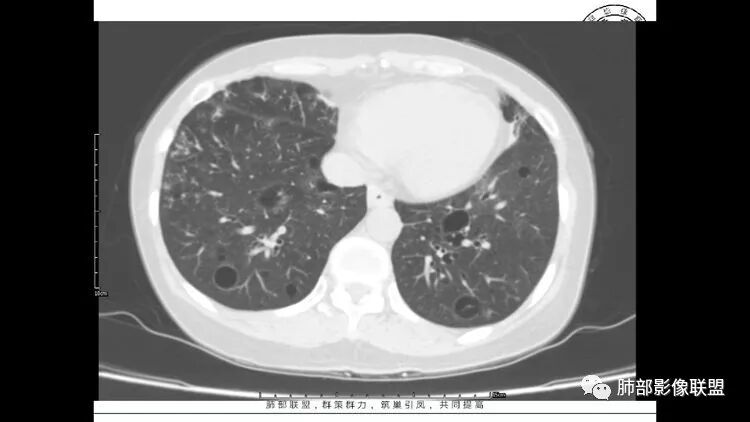

胸CT:1.双肺多发囊性变,以中下肺为主,病变边缘可见肺动脉,部分囊内可见分隔及肺动脉,双下部分肺野周围可见小叶中心结节及树丫征。

2 左肺上叶尖后段 右肺上叶前段 右肺下叶外基底段 结节影,边界清楚,可见柔软毛刺,左肺下叶后基底段混合密度影。

3.纵隔淋巴结肿大?,以主动脉弓为界向上向下增大。

患者中年女性,因右眼红痛1天就诊。胸CT:双肺多发囊性变及结节影,囊以中下肺为多,部分囊内可见分隔及肺动脉,结节部分为实性,部分为混合性,边缘光滑,未见明显毛刺、棘突、胸膜牵拉及血管集束征象。双中下可见支气管扩张及树丫征。淋巴结无明显肿大。综合考虑:一元淋巴细胞间质性肺炎。多元鉴别肺腺癌并转移等恶性病变。

中年女性,双肺多发囊性变,以中下肺为主,病变边缘可见肺动脉,部分囊内可见分隔及肺动脉,左肺上叶较大结节,可见分叶、月牙铲,左肺下叶、右肺中叶磨玻璃病灶,边界清楚,内有空泡,结节,可见尖后段 右肺上叶前段 右肺下叶外基底段 结节影,边界清楚,纵隔淋巴结肿大,

中年女性,因“角膜炎”入院,自用眼液2年,(眼干?)肺部:双肺多发类圆形薄壁气囊+实性结节+GGO,下肺分布为主,纵隔淋巴结肿大,考虑淋巴系统增殖,LIP可能性大,可能继发于干燥综合症;左肺下叶的混合磨玻璃结节形迹可疑,边界清晰,内部疑似空泡,扩张扭曲支气管,极像肺癌,伴双肺转移?待排吧

双肺下叶分布为主的间质改变(磨玻璃影、小叶间隔增厚)、散在气囊影(常有血管贴边)、边界不清小结节